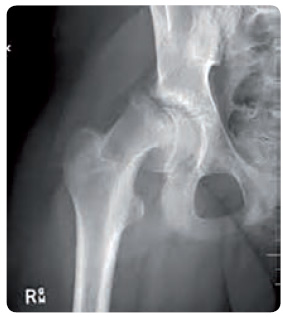

Epifyzeolýza hlavice femuru

Při léčbě růstovým hormonem může vzácně dojít k epifyzeolýze hlavice femuru (obr. 3). Příčinou

může být náhlé růstové urychlení a/nebo základní onemocnění. Při klinickém podezření je nezbytné provést rentgenové vyšetření kyčelních kloubů a při pozitivním nálezu požádat o spolupráci ortopeda.